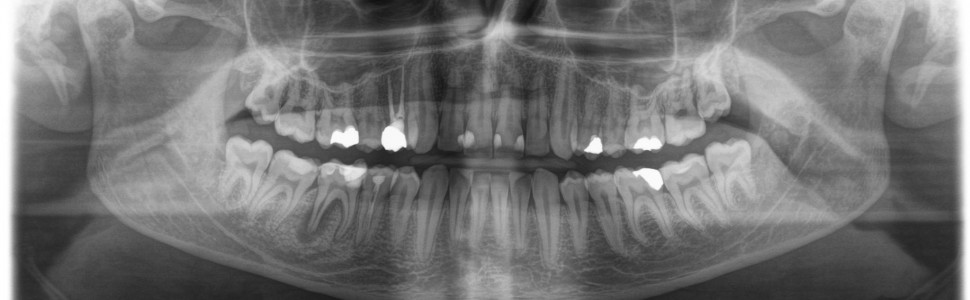

Pierwotne leczenie kanałowe w przypadku resorpcji zapalnej wewnętrznej czy resorpcji części apikalnej przy utracie prawidłowej struktury tego regionu, oraz powtórne leczenie kanałowe przy skomplikowanej, niestandardowej anatomii systemu endodontycznego może sprawiać trudności w codziennej praktyce. Wprowadzenie standardów leczenia w formie poszerzonej diagnostyki radiologicznej (CBCT) czy biozgodnych materiałów, takich jak MTA, do obturacji kanałów korzeniowych przesuwa granice możliwości utrzymania własnego uzębienia pacjenta, pozwalając przywrócić funkcję i zdrowie. W pracy opisano zastosowanie zaawansowanych technik w specjalistycznej praktyce endodontycznej. Zastosowanie biomateriału MTA (Cerkamed) w powyższym przypadku pozwoliło uzyskać szczelność wierzchołkową w leczeniu zęba 46, przy nieregularnym, zresorbowanym wierzchołku oraz połączeniu kanałów DB i DL.

Primary root canal treatment in the case of internal inflammatory resorption or resorption of the apical part with loss of the proper structure of this region, as well as retreatment of the root canal with complicated, non-standard anatomy of the endodontic system may be difficult in everyday practice. The introduction of treatment standards in the form of extended radiological diagnostics (CBCT) or biocompatible materials such as MTA for root canal filling pushes the boundaries of the possibility of maintaining the patient’s own dentition, allowing for the restoration of function and health. The above work describes the use of advanced techniques in specialized endodontic practice. The use of MTA (Cerkamed) biomaterial in the above case allowed to obtain apical tightness in the treatment of tooth 46, with an irregular, resorbed apex and the connection of DB and DL canals.